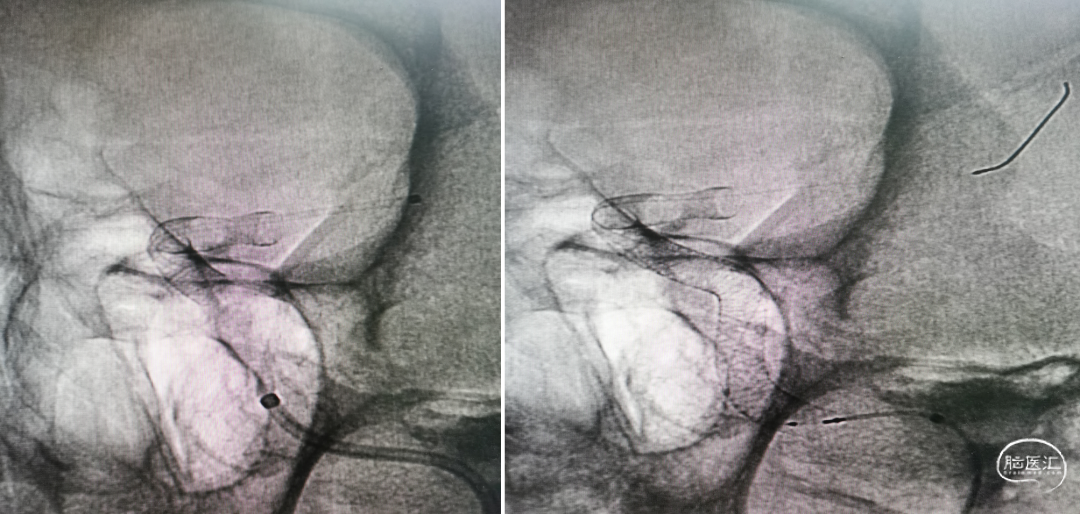

全身麻醉(左侧动脉瘤介入治疗)。

右侧股动脉穿刺置入6F长鞘及颅内支撑导管(Navien™ 颅内支撑导管058 115cm),颅内支撑导管头端置于左颈内动脉C1段行3D旋转,然后将Navien™ 颅内支撑导管头端尽可能的接近病灶。

Synchro 14微导丝引导下将Phenom™ 27微导管置于左侧大脑中动脉M2段,先后置入一枚4.0mm*30mm及一枚4.25mm*35mm Pipeline™ Flex 血流导向密网支架,桥接。

利用微导丝、微导管对支架进行按摩;行Xper CT HiRes Cran.Stent扫描评估。

术中造影

Xper CT HiRes Cran.Stent